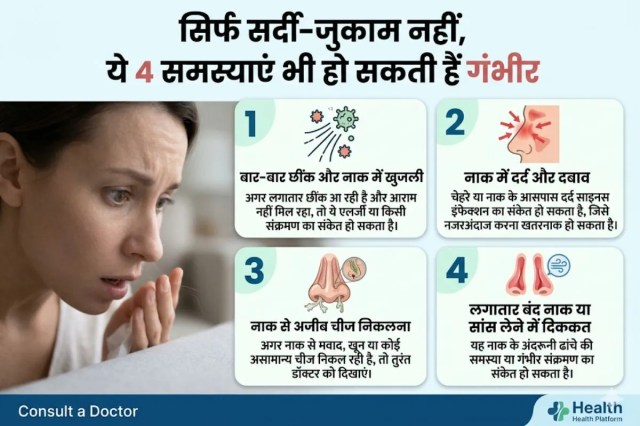

सिर्फ सर्दी-जुकाम नहीं, ये 4 समस्याएं भी हो सकती हैं गंभीर

बार-बार छींक और नाक में खुजली- अगर लगातार छींक आ रही है और आराम नहीं मिल रहा, तो ये एलर्जी या किसी संक्रमण का संकेत हो सकता है।

नाक में दर्द और दबाव- चेहरे या नाक के आसपास दर्द साइनस इंफेक्शन का संकेत हो सकता है, जिसे नजरअंदाज करना खतरनाक हो सकता है।

नाक से अजीब चीज निकलना- अगर नाक से मवाद, खून या कोई असामान्य चीज निकल रही है, तो तुरंत डॉक्टर को दिखाएं।

लगातार बंद नाक या सांस लेने में दिक्कत- यह नाक के अंदरूनी ढांचे की समस्या या गंभीर संक्रमण का संकेत हो सकता है।